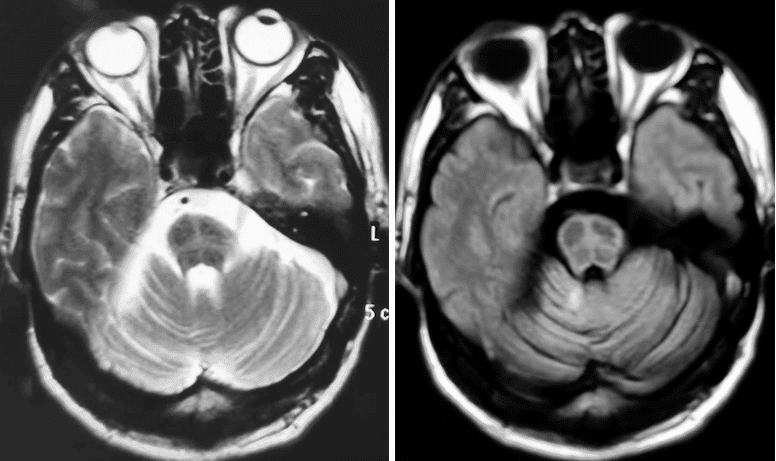

头MRI(2015-10-19 依次为T2、Flair序列)可见桥脑萎缩,已出现“十字征”影像改变。